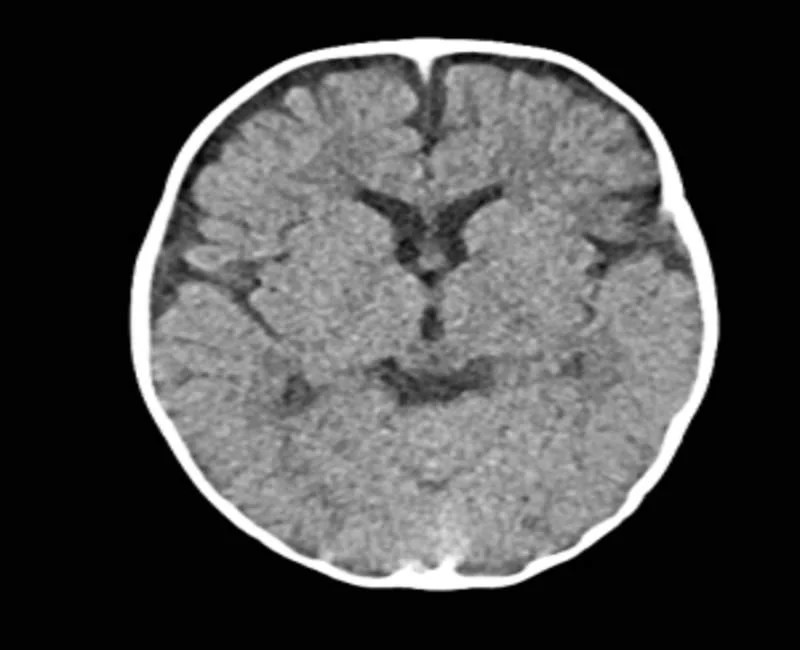

Brain cancer, CT scans Stock Image M134/0465 Science Photo Library What Does A Brain Scan Look Like Learn about basic brain anatomy and function, what a normal brain mri looks like, and some abnormal findings that can be. Radiologists use brain mri to diagnose diseases such as migraine, stroke, microvascular ischemic disease, dementia, multiple sclerosis, epilepsy,. In general, imaging scans provide a visual of the brain that doctors can analyze for signs consistent with dementia. This typically. What Does A Brain Scan Look Like.